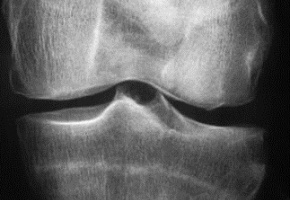

De nombreux essais ont été consacrés aux différentes formes d’arthrose lors du congrès de l’European League Against Rheumatism (Eular), qui vient de se dérouler à Amsterdam du 13 au 16 juin 2018. Certains, faisant notamment appel à des traitements physiques, apportent à nouveau regard à la prise en charge de cette pathologie fréquente. Ainsi, semelles et orthèses pourraient constituer des traitements efficaces dans la gonarthrose

L’utilisation de chaussures spéciales (système Apos) semble prometteuse. Ces chaussures comportent deux demi-balles convexes en caoutchouc, réglables pour chaque patient, sous le talon et l’avant-pied. Cela permet de diminuer les contraintes mécaniques de pression au niveau du genou et contribuent à renforcer les muscles des membres inférieurs. L’étude randomisée Biotok conduite chez 220 patients avec une gonarthrose, a mis en évidence une diminution significative du score de douleur à 6 mois dans le groupe de 111 patients ayant porté ces chaussures : - 1,34 point (p < 0,001) en comparaison du groupe de 109 patients ayant porté des chaussures témoins (S. Reichenbach et al., Université de Bern, Suisse). Les malades devaient porter chacune des catégories de chaussures, à raison de 30 minutes par jour au début de l’étude, puis de plus en plus longtemps (+ 10 minutes par jour chaque semaine), pour atteindre 5 heures par jour en fin d’étude à 6 mois. Le niveau de raideur et la fonction du genou arthrosique ont également été significativement améliorés avec les chaussures Apos. Il reste à déterminer si ces chaussures ont aussi un impact positif sur les lésions structurales de gonarthrose. Par ailleurs, un autre essai randomisé, nommé Ergonomie, s’est intéressé aux effets d’une genouillère articulée, Odra, disponible sur le marché français depuis quelques années (A. Diaz et coll., CHU de Dijon). Cette orthèse réalise une distraction et une rotation du genou afin de réduire les contraintes sur le compartiment fémoro-tibial interne. L’essai a été conduit, sur demande de la Haute autorité de santé (HAS), chez 120 patients français de 7 centres avec une gonarthrose fémoro-tibiale interne douloureuse (plus de 40 mm sur l’échelle visuelle analogique, EVA). La moitié des patients a porté l’orthèse tandis que l’autre recevait des soins usuels, médicamenteux ou non. A un an, la réduction de la douleur évaluée sur l’EVA (critère de jugement principal de l’étude) a été significativement plus importante dans le groupe ayant porté la genouillère (différence de 13,1 ± 4,9 mm par rapport au groupe témoin, p < 0,01). Le niveau fonctionnel, et la qualité de vie ont aussi été améliorés après port de l’orthèse. En outre, les malades ont utilisé moins d’analgésiques. En revanche, il n’a pas été noté de différence concernant la consommation d’Ains et les injections d’acide hyaluronique. Les genouillères sont parfois mal acceptées et peuvent engendrer des effets indésirables cutanés. Dans cet essai, l’observance a été correcte (port de la genouillère en moyenne 5,7 h par jour au cours des 6 premiers mois et 5,3 heures entre 6 et 12 mois). Mais, 13 % des patients ont cessé de la porter en raison d’effets cutanés.   Inefficacité de la radiothérapie à faible doses   D’autres stratégies thérapeutiques, dont certaines audacieuses, montrent des résultats décevants. Une équipe néerlandaise n’a pas hésité à évaluer une radiothérapie à faible dose (6 séances de 1 gray sur 2 semaines) chez des patients symptomatiques avec une arthrose digitale (n = 56) ou une gonarthrose (n = 55) (M. Minten et coll., Sint Maartenskliniek, Pays-Bas). Pourtant, aucune différence significative n’a été relevée à 3 mois, en termes de taux de réponse ou de présence de signes inflammatoires en échographie ou en IRM, par rapport au groupe contrôle ayant reçu en double aveugle une radiothérapie fictive. L’étude ZAP2, menée chez 223 patients avec une gonarthrose avec œdème sous-chondral osseux en IRM, a aussi échoué à trouver un effet positif significatif en termes de réduction de la douleur, ou d’indice fonctionnel à 24 mois, après injection d’acide zolédronique (G. Cai et coll., Université de Tasmanie, Hobart, Australie). Pourtant, un premier essai de 6 mois en 2012 avait suggéré un impact positif de ce bisphosphonate. Par ailleurs, une étude de cohorte canadienne a comparé 7743 patients arthrosiques à 23 229 sujets témoins non arthrosiques montre que le risque cardiovasculaire (RCV) est augmenté chez les sujets malades : il est multiplié par 1,23 globalement par rapport aux sujets non arthrosiques. Cet essai suggère, en outre, que 68 % de l’élévation du RCV, observée chez ces patients, implique la prise de médicaments anti-inflammatoires non stéroïdiens (Ains). "Ces résultats posent question car cette classe thérapeutique est largement utilisée dans l’arthrose », a admis le Pr Aslam Anis (Université de Colombie Britannique, Vancouver, Canada), « et ils ont été retrouvés après ajustement pour l’âge, le sexe, le statut socio-économique, l’indice de masse corporelle (IMC), et même la présence de comorbidités accroissant le risque cardiovasculaire : HTA, Bpco, diabète...". Un nouvel axe : inhiber la voie Wnt Enfin, les perspectives offertes par les biothérapies ne sont pas oubliées dans le domaine de l’arthrose. Un essai de phase 2 entrepris chez 455 patients avec une gonarthrose laisse d’ailleurs penser qu’une petite molécule, SMO4690, capable d’inhiber la voie Wnt impliquée dans la différenciation des ostéoblastes et des chondrocytes, pourrait après injection intra-articulaire réduire de façon prolongée la douleur arthrosique et améliorer la fonction du genou (S. Kennedy et coll., San Diego, États-Unis).

Parfois négligée, l’arthrose doit pourtant être prise en charge, car dans les formes sévères, ses répercussions psychologiques sont non négligeables. L’analyse de 1652 patients de la cohorte américaine Osteoarthritis Initiative confirme ainsi qu’une diminution des performances physiques et la présence d’une douleur, ou de lésions structurales importantes en radiographie, s’associe à un risque nettement accru de dépression dans la gonarthrose sévère (A. M. Rathbun, et coll., Université du Maryland, Baltimore, États-Unis). Les patients étaient classés en fonction de la sévérité de la maladie jugée sur la vitesse de marche, le pincement articulaire, et la douleur. Entre le dernier (malades les plus touchés) et premier quintile (les moins touchés), la probabilité de survenue d’une dépression était ainsi multipliée par 1,80 pour le critère de la vitesse de marche, 2,10 pour le pincement articulaire, et 2,21 pour la douleur.